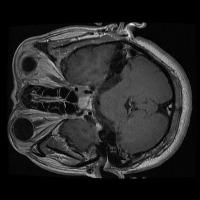

tumor otak Computer Vision Project

Here are a few use cases for this project:

Medical Diagnostics: This model can be used for assisting healthcare professionals in diagnosing brain tumors by classifying them into glioma, pituitary, or meningioma, which can save time and lead to early and accurate disease diagnosis.

Health Monitoring Software: It can be implemented in health and wellness apps to monitor a patient's MRI scans regularly, thus providing an early warning system for possible tumor growth.

Training medical students and resident doctors: The model can be used as a training tool for medical students and resident doctors to better understand and identify different types of brain tumors from MRI images.

Research Studies: It may be used by scientists and researchers for creating more focused and comprehensive studies on brain tumors, contributing to advancements in the respective field of study.

Telemedicine: This model can be helpful in telemedicine portals where expert opinion may be lacking. The model could provide initial diagnosis based on MRI scans before a patient consults with a healthcare professional.